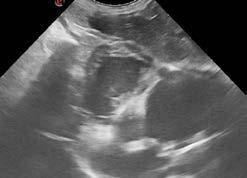

Due to the elevated liver enzyme values, abdominal ultrasound was recommended.

On ultrasound, the liver was enlarged with a diffuse patchy parenchyma (Figure 1). There was sonographic evidence of renal cysts, splenic nodules, and pancreatic changes consistent with chronic pancreatitis. The cause of vomiting and diarrhoea remained open, but due to hepatic changes, fine needle aspirates of liver were taken and submitted for cytology.

Surprisingly, the cytology results returned for Mojo revealed Dirofilaria immitis microfilariae within the hepatic parenchyma (Figure 2). Although an unexpected finding, these results were consistent with heartworm infestation. Based on these results, heartworm antigen test was added, and it came back positive. Due to the presence of circulating microfilariae in the liver, a microfilariae blood test was not performed.